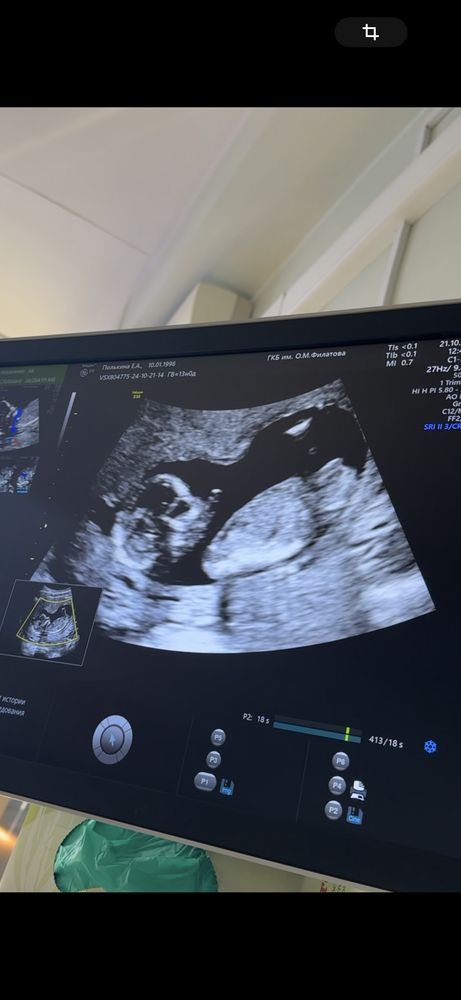

Пол на 15 неделе

Мальчик❤️у мена такие же снимки)

Мальчишка у вас💙

Мальчик, у меня такое же было узи

У девочек ничего между ног нет, судя по снимку)

Вижу мальчика

могут, формирование половых органов ещё не завершилось, плюс девочек бывают опухшие половые губы и большой клитор, плюс в некоторых ракурсах пуповина выглядит так же. но я по фото тоже мальчика вижу)

Татьяна, да тоже вижу мальчика, но врач сказал что бывает что половые органы опухшие и ближе 20 неделе уже точно скажут.

Кто же у нас?) Второй скрининг